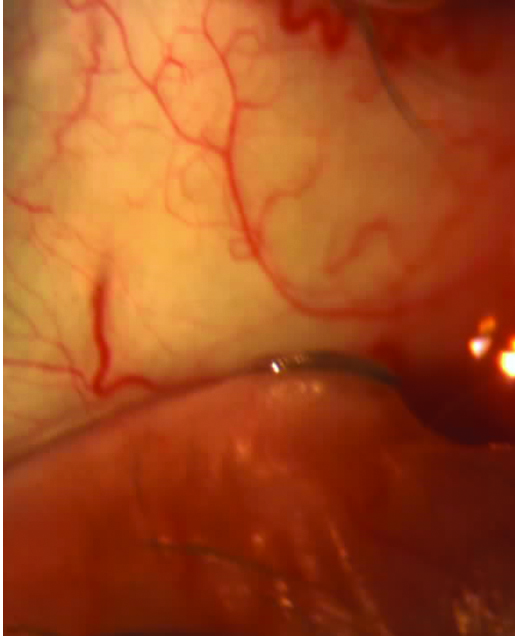

Con el rosa de bengala o la lisamina verde se puede determinar además el grado de fricción palpebral que se expresa al evertir el párpado superior y observar si el colorante tiñe el borde interno palpebral (Fig. 9).

Figura 9: Tinción con lisamina zona de fricción